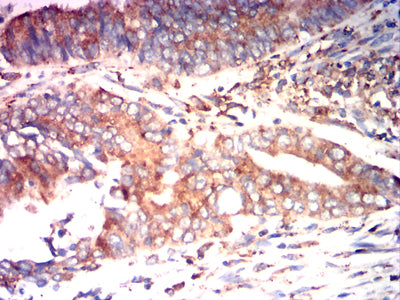

Immunohistochemical analysis of paraffin-embedded human rectal cancer tissues using P4HB mouse mAb with DAB staining.